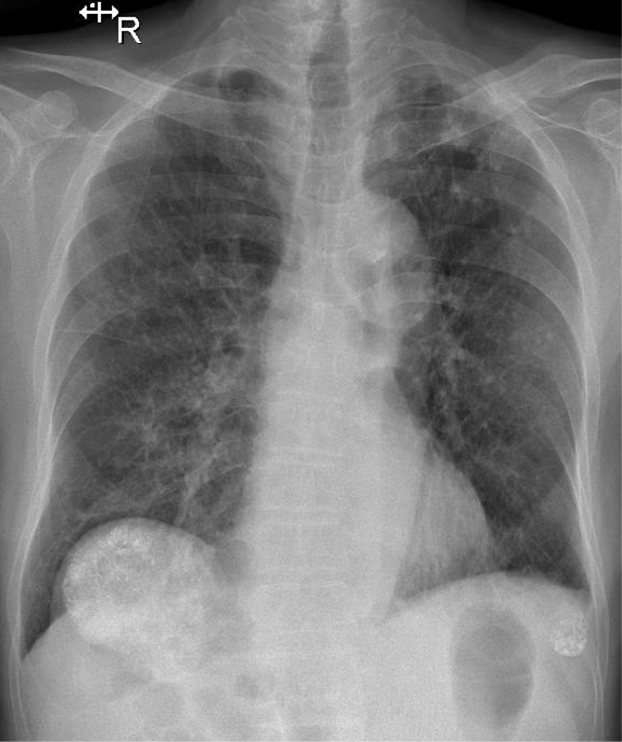

1-Xơ vôi thùy trên phổi (T) 2-Khí phế thũng rải rác hai phổi 3-Cung động mạch chủ đóng vôi 4-Gãy cũ 1/3 ngoài xương đòn (T) 5-Khối cản quang đậm độ cao vòm hoành (P) khả năng K gan đã TOCE